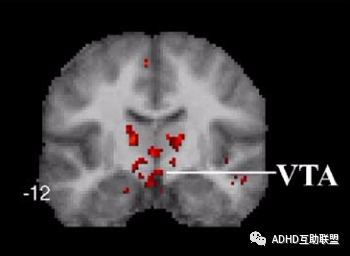

1.目前多认为多巴胺(DA)的功能不足是 ADHD 主要发病机制之一,功能磁共振研究发现,音乐可强烈激活伏隔核(NAC)、腹侧被盖区(VTA)和下丘脑、脑岛,伏隔核和腹侧被盖区的激活会帮助多巴胺的释放,从而改善ADHD儿童的核心症状。

研究发现,和听杂乱的音乐相比,志愿者在听古典音乐时,大脑伏隔核和包括腹侧被盖区、下丘脑和眶额叶在内的相关中脑边缘结的大脑网络被激活(伏隔核和大脑奖赏系统有关)。这些脑区负责奖赏、自我管理和认知处理。

(和听杂乱的音乐相比,志愿者在听古典音乐时,伏隔核和包括腹侧被盖区、下丘脑和眶额叶在内的相关中脑边缘结构的大脑网络被激活。)